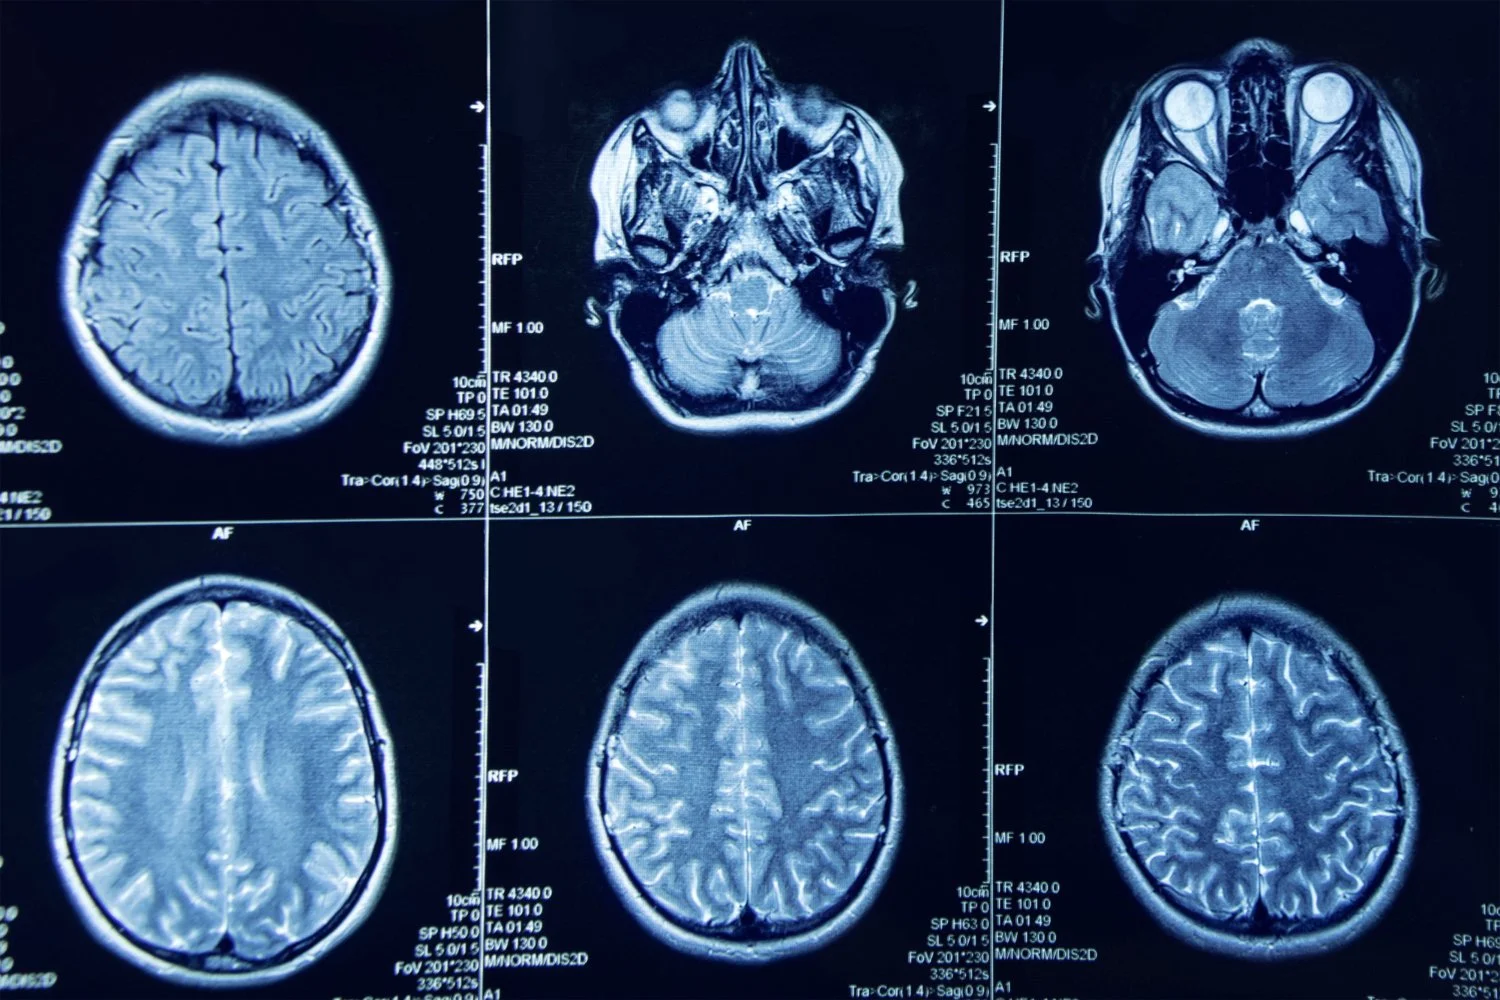

Expert Treatment for Brain Tumors, Spinal Conditions, Herniated Disk, Nerve Injury, Tremor & Parkinson’s.

When you are dealing with a complex brain, spine, or nerve condition, you need more than just standard medical advice. You need clear, trustworthy answers and a path forward that makes sense for you.

View the list of brain, spine and nerve conditions that Dr. Gorecki can help you address.